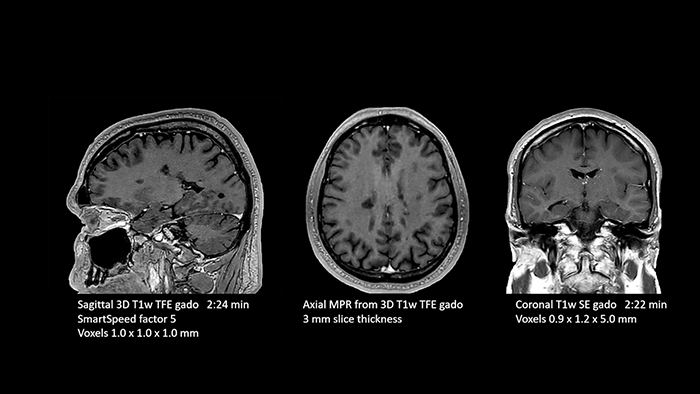

Dr. Schröter points out that a more confident diagnosis requires high-quality images with more diagnostic information. “Philips SmartSpeed provided that to us. AI denoises the clinical images without losing any important data, resulting in high-resolution images. It keeps all the information we need and makes the images better. We can apply SmartSpeed to almost all sequences. That is a big step forward! We use it for example in 3D imaging and in diffusion-weighted imaging, to dramatically reduce scan time or increase image resolution, which is quite useful. There are small lesions that we would certainly have seen without SmartSpeed, however it would have taken us longer to properly diagnose. In 3D MSK images with extremely high resolution, we uncover the finest anatomical structures and can thus report very detailed findings.”

Another important part of MR Workspace is the graphics processing unit (GPU), which allows on-the-fly reconstruction times for images acquired with SmartSpeed. “In addition to seeing razor-sharp images on the large 4K monitor, we also have better and faster reconstruction of the images. Using this extremely high resolution, we sometimes have sequences with up to 800 individual images. The GPU then manages to convert them in a matter of seconds into multiplanar reconstructions. Very impressive.”